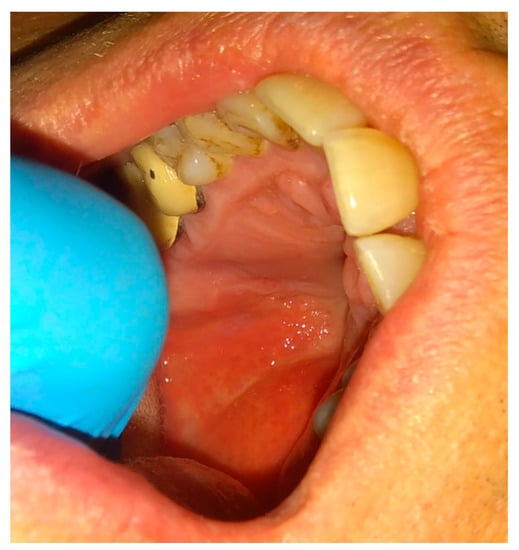

The rotation of the palatal flap can be used to solve some problems with the closure without buccal depth loss and esthetic function reduction. A full-thickness flap that contains the palatal artery is a good option to close an oro-antral communication. However, this procedure creates great morbidity and requires a long post-operative care period of the donor site on the palate. Flexibility possibilities of the palatal flap are limited, which forces the surgeon to create a large incision to assure the rotation of a sufficient amount of tissues. Second, the palatal defect heals via granulation, which is also troublesome for the patient. The location on the vestibular sulcus of the maxillary alveolar bone and the large size of the lesion support the choice of the pedicled buccal fat pad flap technique [21]. In some cases of bigger maxillary sinus wall deficiencies, the suturing can be troublesome, especially when it causes severe buccal narrowing or is sutured with tension. A free-of-tension suturing of any oroantral communication is easily achieved with the BFP and can be easily used for suturing in any dental surgery (Figure 1, Figure 2, Figure 3 and Figure 4).

Figure 3. The bone defect was covered with the Bichat fat pad after mobilization. The entire defect will be sutured with vertical mattress sutures to the palate to ensure its proper position.